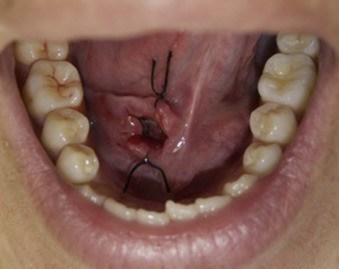

Marsupialization involves cutting open the cyst so it can drain. Once the fluid has drained, stitches are added to the edges of the incision to keep it open, which prevents another cyst from growing there.